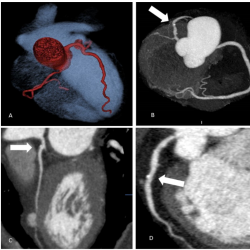

Fig. 1

Coronary arteries’ scanning images (Group 1 – overweight patients).

A – Coronary arteries’ 3D reconstruction. Patient’s BMI 29.1 kg/m2; 80-kV, effective dose 1.2 mSv.

B – Coronary arteries’ 3D reconstruction. Patient’s BMI 25.1 kg/m2; 80-kV, effective dose 0.95 mSv; calcified plaque in LAD S6 (labelled by white arrow).

C – Multiplanar curved reconstruction of LAD coronary artery. LAD S6 mixed plaque, 20% stenosis (labelled by white arrow). Patient’s BMI 28.2 kg/m2, 100-kV.

D – Multiplanar curved reconstruction of LAD coronary artery. LAD S7 calcified plaque, 25% stenosis (labelled by white arrow). Patient’s BMI 25.1 kg/m2, 80-kV.

In our study, we tested the feasibility of low doses protocols (80-kV and 100-kV) depending on BMI, and demonstrated a significant reduction of radiation dose 35% and 41% versus standard 100-kV and 120-kV protocols: (1.1 mSv [0.9–1.2] (80-kV) versus 1.7 mSv [1.0–2.0] (100-kV) and 1.6 mSv [1.4–1.9] (100-kV) versus 2.7 mSv [2.1–3.0] (120-kV)). Our data demonstrate that in an overweight patient group, an ultra-low dose protocol (radiation dose reduction of 35%) scanning results are feasible enough. It allows the identification of patients with significant and intermediate CAD, as well as the identification of patients with no-, single-, or multi-vessel disease (see Fig. 1). The segmental analysis provides for the severity and range of CAD while showing the location of the disease. This complementary information becomes significant for clinical decision-making and, if necessary, for selecting the appropriate revascularization procedure (percutaneous intervention or bypass surgery) for patients.